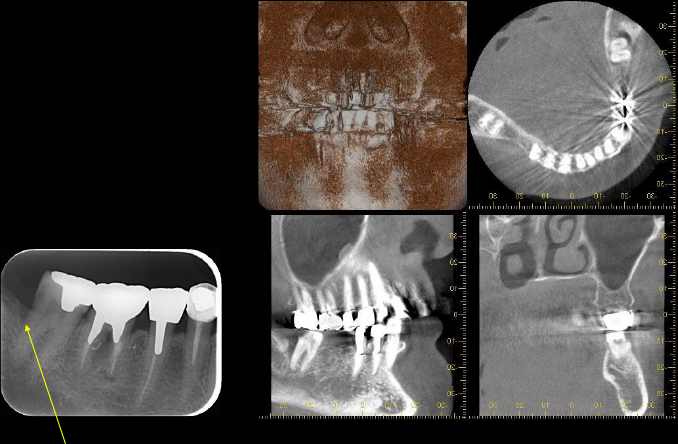

デンタルおよびCT所見

before before |

after after |

術前 術前 |

術後8カ月 術後8カ月 |

歯周病により失われた歯槽骨が骨様組織により改善されているように思われます。

右の下奥歯には深い歯周ポケットが残っています。

レントゲン写真では矢印の位置ぐらいには骨がありそうに見えますが、CTにて詳しく調べてみると矢印の位置まで歯周病が進行して骨が破壊されていることがわかります。

患者さんと相談した結果、歯周組織再生療法を希望されたため、施術させていただくことになりました。

術直後のレントゲン写真です。

術後8か月 術後8か月 |

術後15か月CT所見 術後15か月CT所見 |

術前 術前 |

術後15か月CT所見 術後15か月CT所見 |

術前で破壊されていた部分に骨の再生が認められるため、黒かった部分が白くなっていることがわかります。

再生療法時 骨が失われている部位 骨が失われている部位 |

再生療法後 再生した部位 再生した部位 |

| 失われていた骨の再生が認められます。 | |

CT所見で見られたのと同様に再生療法を行った部位にみられた骨欠損は骨様組織にて満たされていることがわかります。